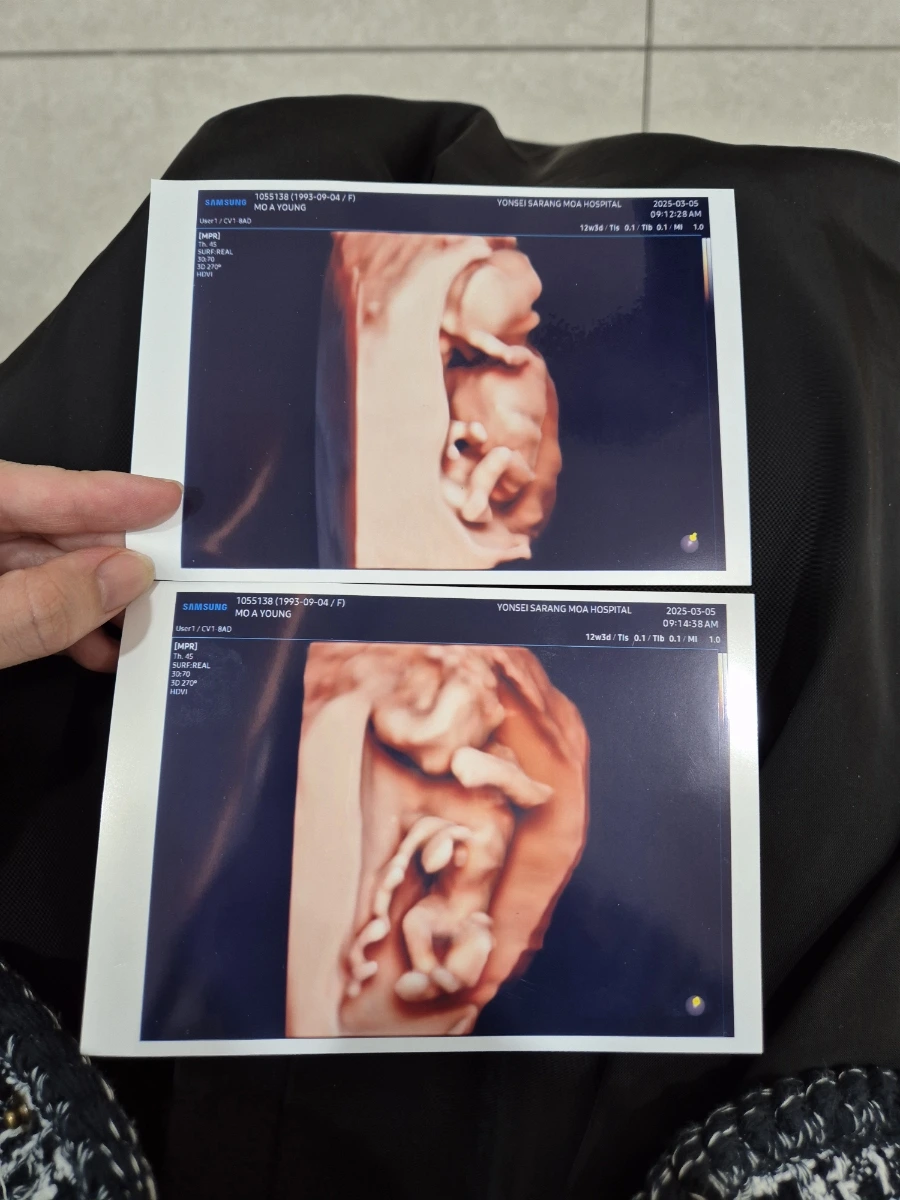

그리고 가장 최근인 12주 차에 만난 알콩이. 이날은 병원에서 20분이 넘게 긴 시간 동안 알콩이를 만나게 해 주셨다. 목둘레는 정상인지, 손가락 발가락은 잘 자리 잡았는지, 심장은 잘 뛰는지 확인해 주셨고 모두 다 건강하다는 소식을 들어서 정말 행복하고 감사한 날이었다.

입체 초음파로 만난 알콩이는 손으로 얼굴을 자꾸 가리고 다리를 쪼그렸다 폈다 하면서 엄마아빠를 위해 자태를 뽐내줬다. 남편은 벌써 아빠 닮아 손발과 몸이 길쭉길쭉한 것 같다고 팔불출 같은 소리를 한다.. 다음 검진인 16주 차에는 드디어 알콩이의 성별을 알 수 있는 시기다. 딸일까 아들일까 궁금하긴 하지만 알콩이가 그저 건강하게만 자라줬으면 하는 게 엄마와 아빠의 마음이야 :)